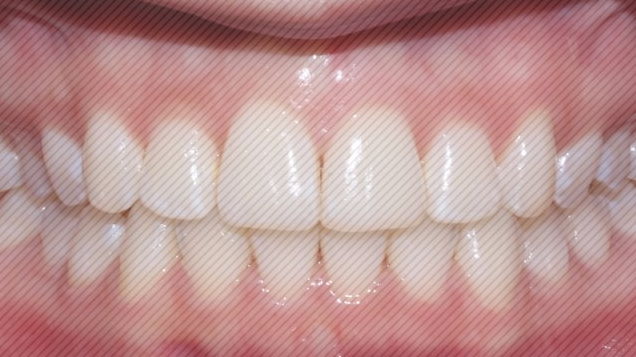

2D교정 교정기간 : 4개월

상악 오른쪽 앞니의 부분 돌출도

이상없이 고르게 교정이

완료 되었습니다.

하악 크라우딩

(자리가 없어 덧난 경우) 도

예쁘게 제자리를 찾아 갔습니다.

4개월만에 개선된 모습을 보니

환자분도 굉장히 만족해하셨는데요.

대신 그만큼 유지장치도

잘 착용해주시고

관리도 잘 해주셔야 한다는 점!

잊지 마세요 :)